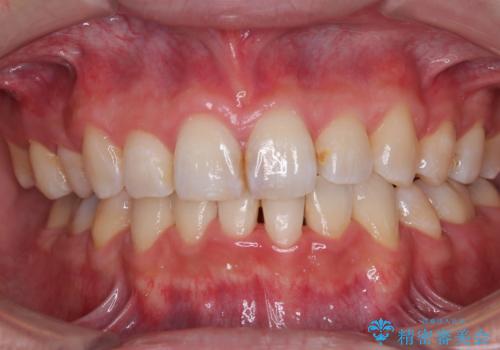

顎が左右にずれた咬み合わせ ハーフリンガルの抜歯矯正

裏側装置での交叉咬合改善は非常に困難なもので、頻繁に装置の脱落がありました。

それでも想定以上に治療期間は長期化せず、咬み合わせも口元も満足のいく仕上がりとなりました。